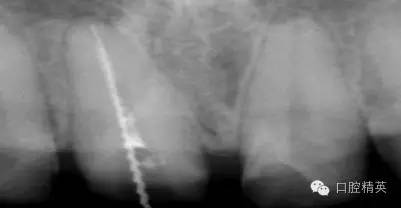

根管治療更是牙體修復(fù)的基礎(chǔ),根據(jù)術(shù)前診斷,對需要做根管治療的或有必要重新做根管治療的,一定要做到恰充,消除隱患,避免將來冠修復(fù)好后,出現(xiàn)根尖炎癥的問題(見圖3、4、5)。在基礎(chǔ)工作做好后,接下來開始牙體預(yù)備,根據(jù)跟個人習慣,選擇合適的車針(圖6、7)。